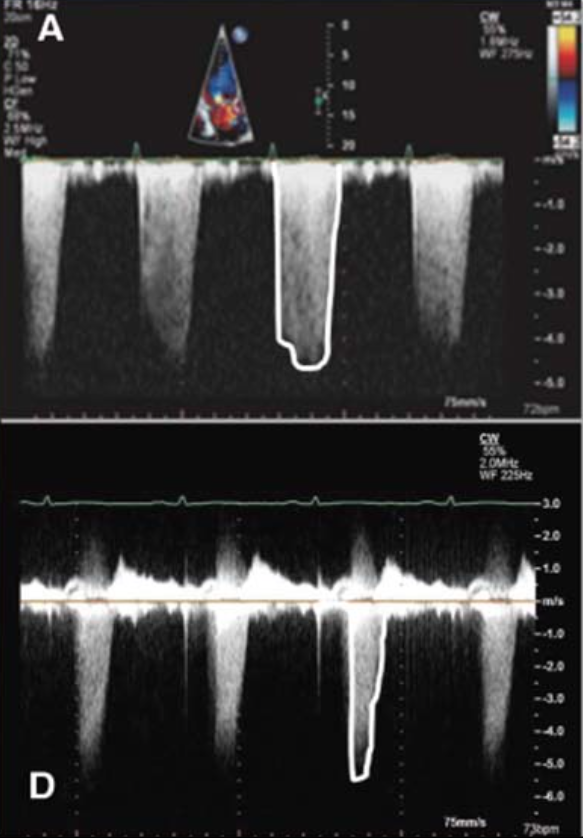

Diagnosis in each picture

PV systolic damping and Systolic flow reversal (from severe MR- goes UNDER the baseline)